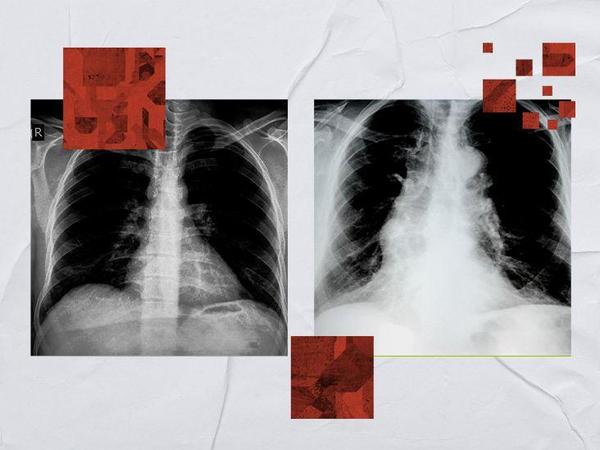

Chest X-ray for tuberculosis (TB): What to expect, results, and more

X-rays can help doctors identify TB infections. They look for specific characteristics in these images to make a diagnosis. TB is an infectious disease that primarily affects the lungs, although it can sometimes spread to other parts of the body. The condition is a significant public health concern with significant global effects. It affects annually, leading to considerable health issues and mortality. In some cases, TB can be life threatening.